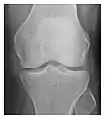

Occult osseous injuries may result from a direct blow to the bone by compressive forces of adjacent bones against one another or by traction forces during an avulsion injury. Lesions in the tibial plateau, hip, ankle, and wrist are often missed. In a tibial plateau fracture, any disruption of the posterior and anterior cortical rims of the plateau should be sought. Impaction of subchondral bone will appear as an increased sclerosis of the subchondral bone (Figure 1). In the hip, posterior acetabular fractures also present subtle radiographic findings. The acetabular lines should then be carefully examined keeping in mind that the posterior rim, which is harder to see on X-rays, is more frequently fractured than the anterior rim (Figure 2). In the wrist, detection of carpal bone fractures is often challenging, with up to 18% of scaphoid fractures radiographically occult. Carpal fractures, especially the scaphoid, are associated with the risk of avascular necrosis. In apparently normal wrist radiographs from symptomatic patients, if there is history of a fall on an outstretched hand with pain in the anatomic snuffbox, suggesting scaphoid injury, the initial examination with posteroanterior, lateral, and pronation oblique views must be complemented by other specific views such as supination oblique and the "scaphoid" view A careful examination of cortices for evidence of discontinuity or offset and cancellous bone for lucency is necessary (Figure 3).[1]

Figure 3: A 26-year-old man presenting with wrist pain after being assaulted. (a) Initial anteroposterior radiograph shows a subtle linear lucency within the scaphoid extending to the scaphocapitate articular surface that was overlooked (arrow). (b) Initial "scaphoid" view was negative. (c) Followup anteroposterior radiographs, 12 days later, shows obvious scaphoid fracture (arrows).[1]